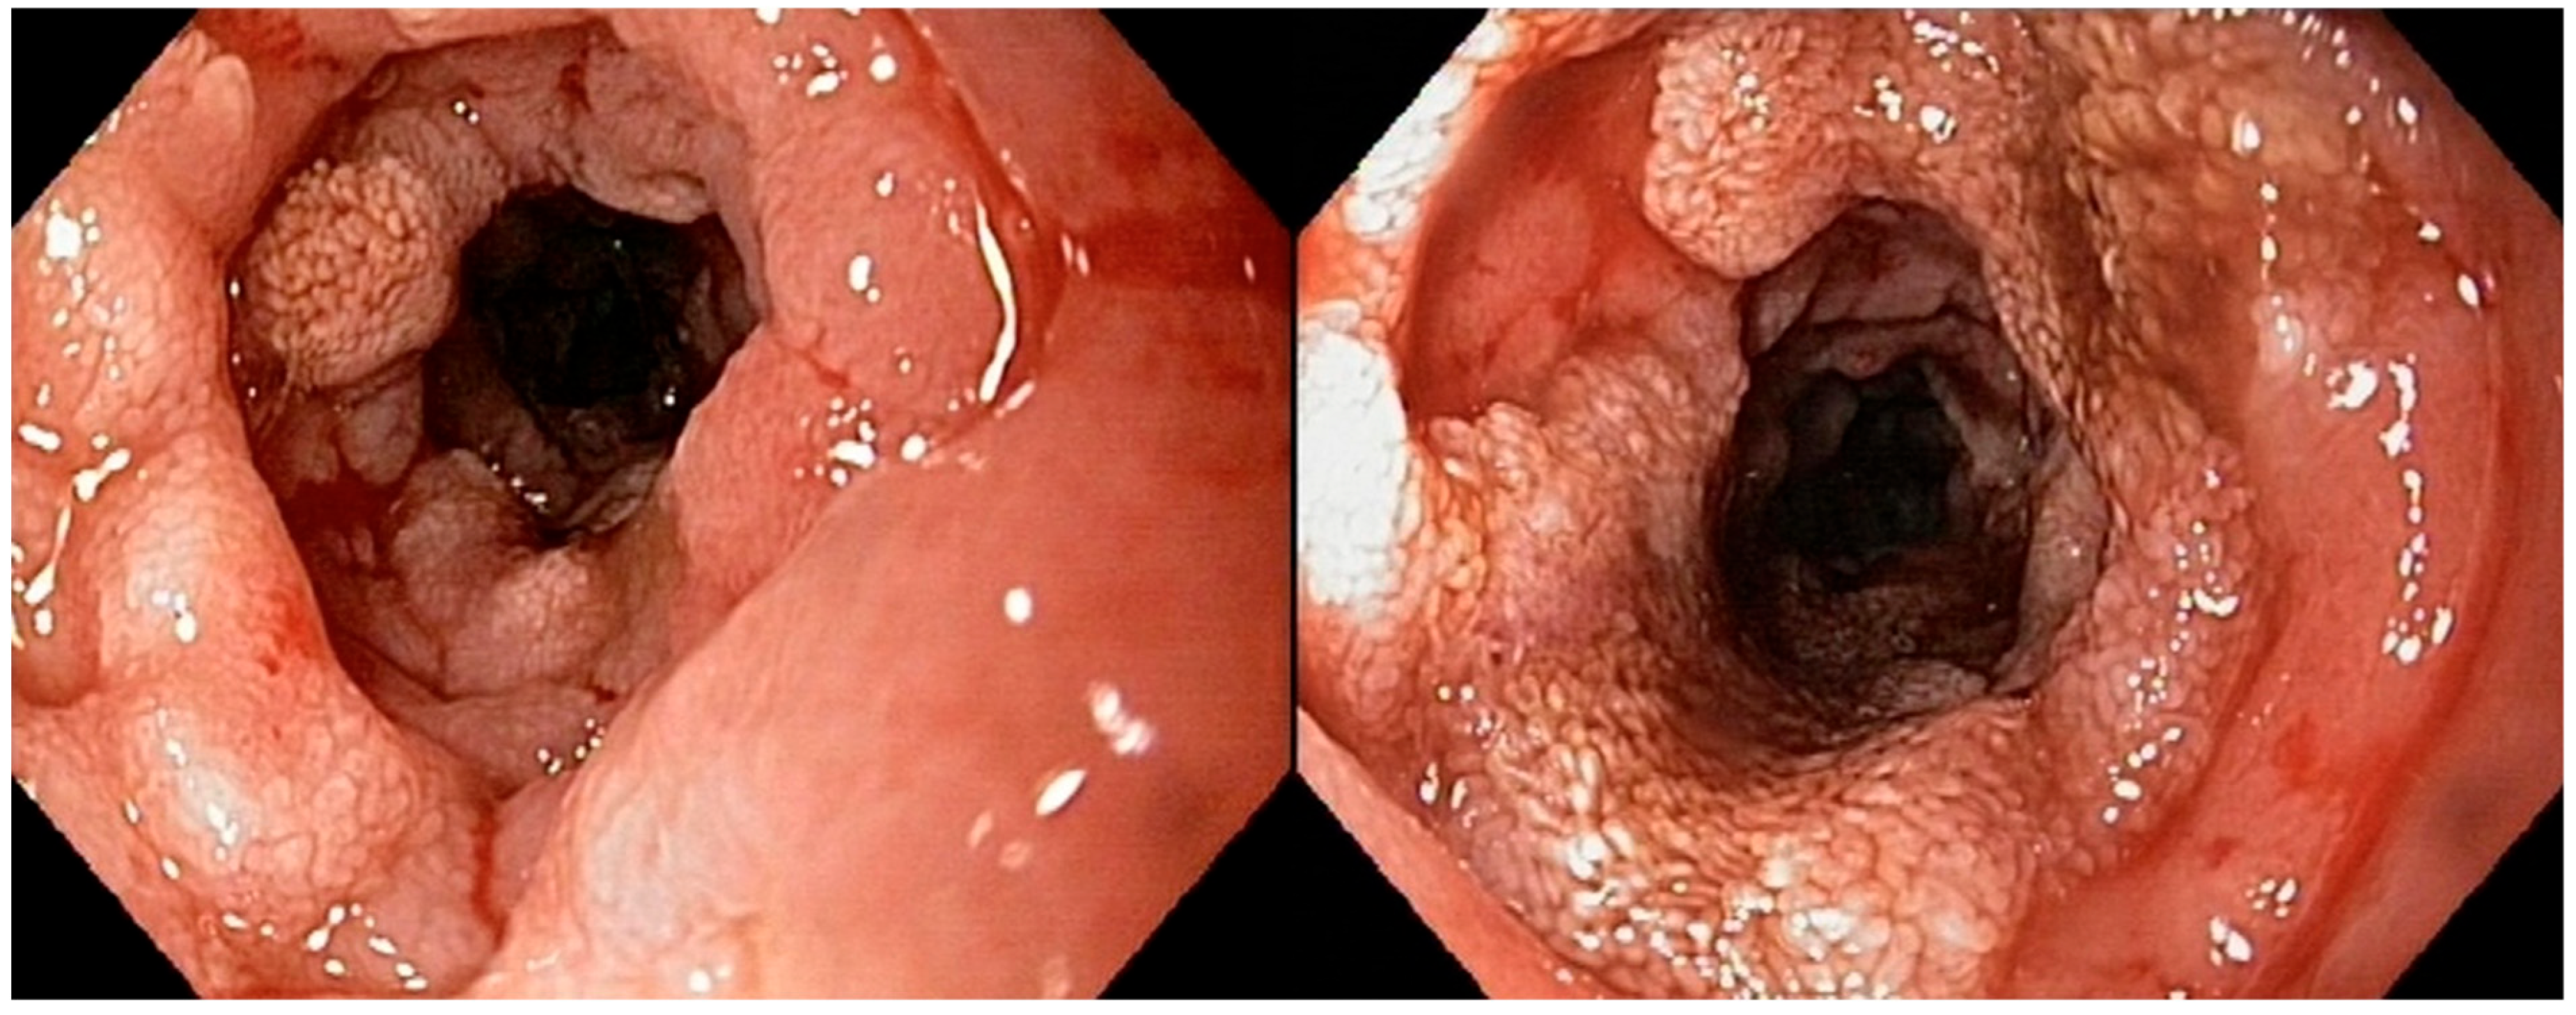

All of the endoscopic findings are summarized in Table 3. Figure 2 illustrates a severe alteration in the granularity of the duodenal mucosa during duodenoscopy. Duodenal lacteal dilatation was observed in one dog (6%). A “cobblestone” appearance of the duodenal mucosa was identified in nine dogs (53%) (Figure 3). No dog developed colonic stricture or intussusception.

A “cobblestone” appearance of the duodenal mucosa was identified in nine dogs with duodenal lymphoma (9/15; 60%) and in neither of the two dogs without duodenal involvement who underwent gastroduodenoscopy. All nine of these dogs (100%) with a “cobblestone” appearance of the duodenal mucosa had confirmed duodenal involvement from intermediate- to large-cell lymphoma. A comparative analysis of clinical and histological quantitative parameters between dogs with and without this endoscopic feature is shown in Table 5. Dogs with a “cobblestone” appearance of the duodenal mucosa showed a significantly lower plasma albumin concentration (mean, 18.8 g/L; SD, 4.32; and range, 13–26) compared to dogs without a “cobblestone” appearance (mean, 25.3 g/L; SD, 4.3; and range, 19–31; p = 0.007; Figure 6a). They also had a significantly higher CCECAI score (mean, 11.1; SD, 1.45; and range, 9–13) than dogs without a “cobblestone” appearance (mean, 8.0; SD, 2.27; and range, 5–12. p = 0.004; Figure 6b). Age, body weight, serum cobalamin concentration, and Ki67 score did not differ between groups (Table 5).

One of our main aims was to provide an endoscopic description of lesions observed with diffuse AL. To the authors’ knowledge, this is the second study to describe the endoscopic features of AL in dogs, and the first to specifically document endoscopic findings in cases with a diffuse form of the disease. The only previously published study included seven dogs with AL, four of which exhibited a “cobblestone” appearance of the duodenal mucosa, consistent with histologically confirmed duodenal infiltration [23]. Our findings expand upon these preliminary observations by focusing on the diffuse form of the disease and systematically correlating endoscopic features with histopathological and immunohistochemical data. In our study, the duodenum was the most frequently affected segment of the gastrointestinal tract, with lymphomatous infiltration of the mucosa observed in 15 out of 17 dogs (83%). Altered mucosal granularity was the most commonly reported abnormality and was present in all dogs with duodenal lymphoma. Severe changes in granularity were reported in 41% (7/17) of dogs, one of which had a small- to intermediate-cell duodenal lymphoma. A “cobblestone” appearance of the duodenal mucosa was noted in 9 out of 17 dogs (53%) and was significantly associated with lower plasma albumin concentrations and higher CCECAI scores. All affected dogs were diagnosed with intermediate- to large-cell duodenal lymphoma. Therefore, a “cobblestone” pattern in the duodenum should be considered a potential indicator of disease severity. This endoscopic feature has already been reported in dogs with duodenal lymphoma, leading authors to propose that AL should be strongly suspected when a solitary mass or a cobblestone appearance is observed on endoscopic examination [23]. However, because our study did not include dogs with chronic inflammatory enteropathies, we cannot determine whether this feature is specific to lymphoma. A comparative study including both healthy control dogs and dogs with non-neoplastic chronic enteropathies would be required to assess the diagnostic relevance of this pattern. Furthermore, due to the limited number of cases with gastric, ileal, or colonic lymphoma in our study, no firm conclusions can be drawn regarding the endoscopic appearance of these segments.

Figure 3. Duodenoscopy of dog n°6 (confirmed large-T-cell duodenal lymphoma): “cobblestone” appearance of the duodenal mucosa.